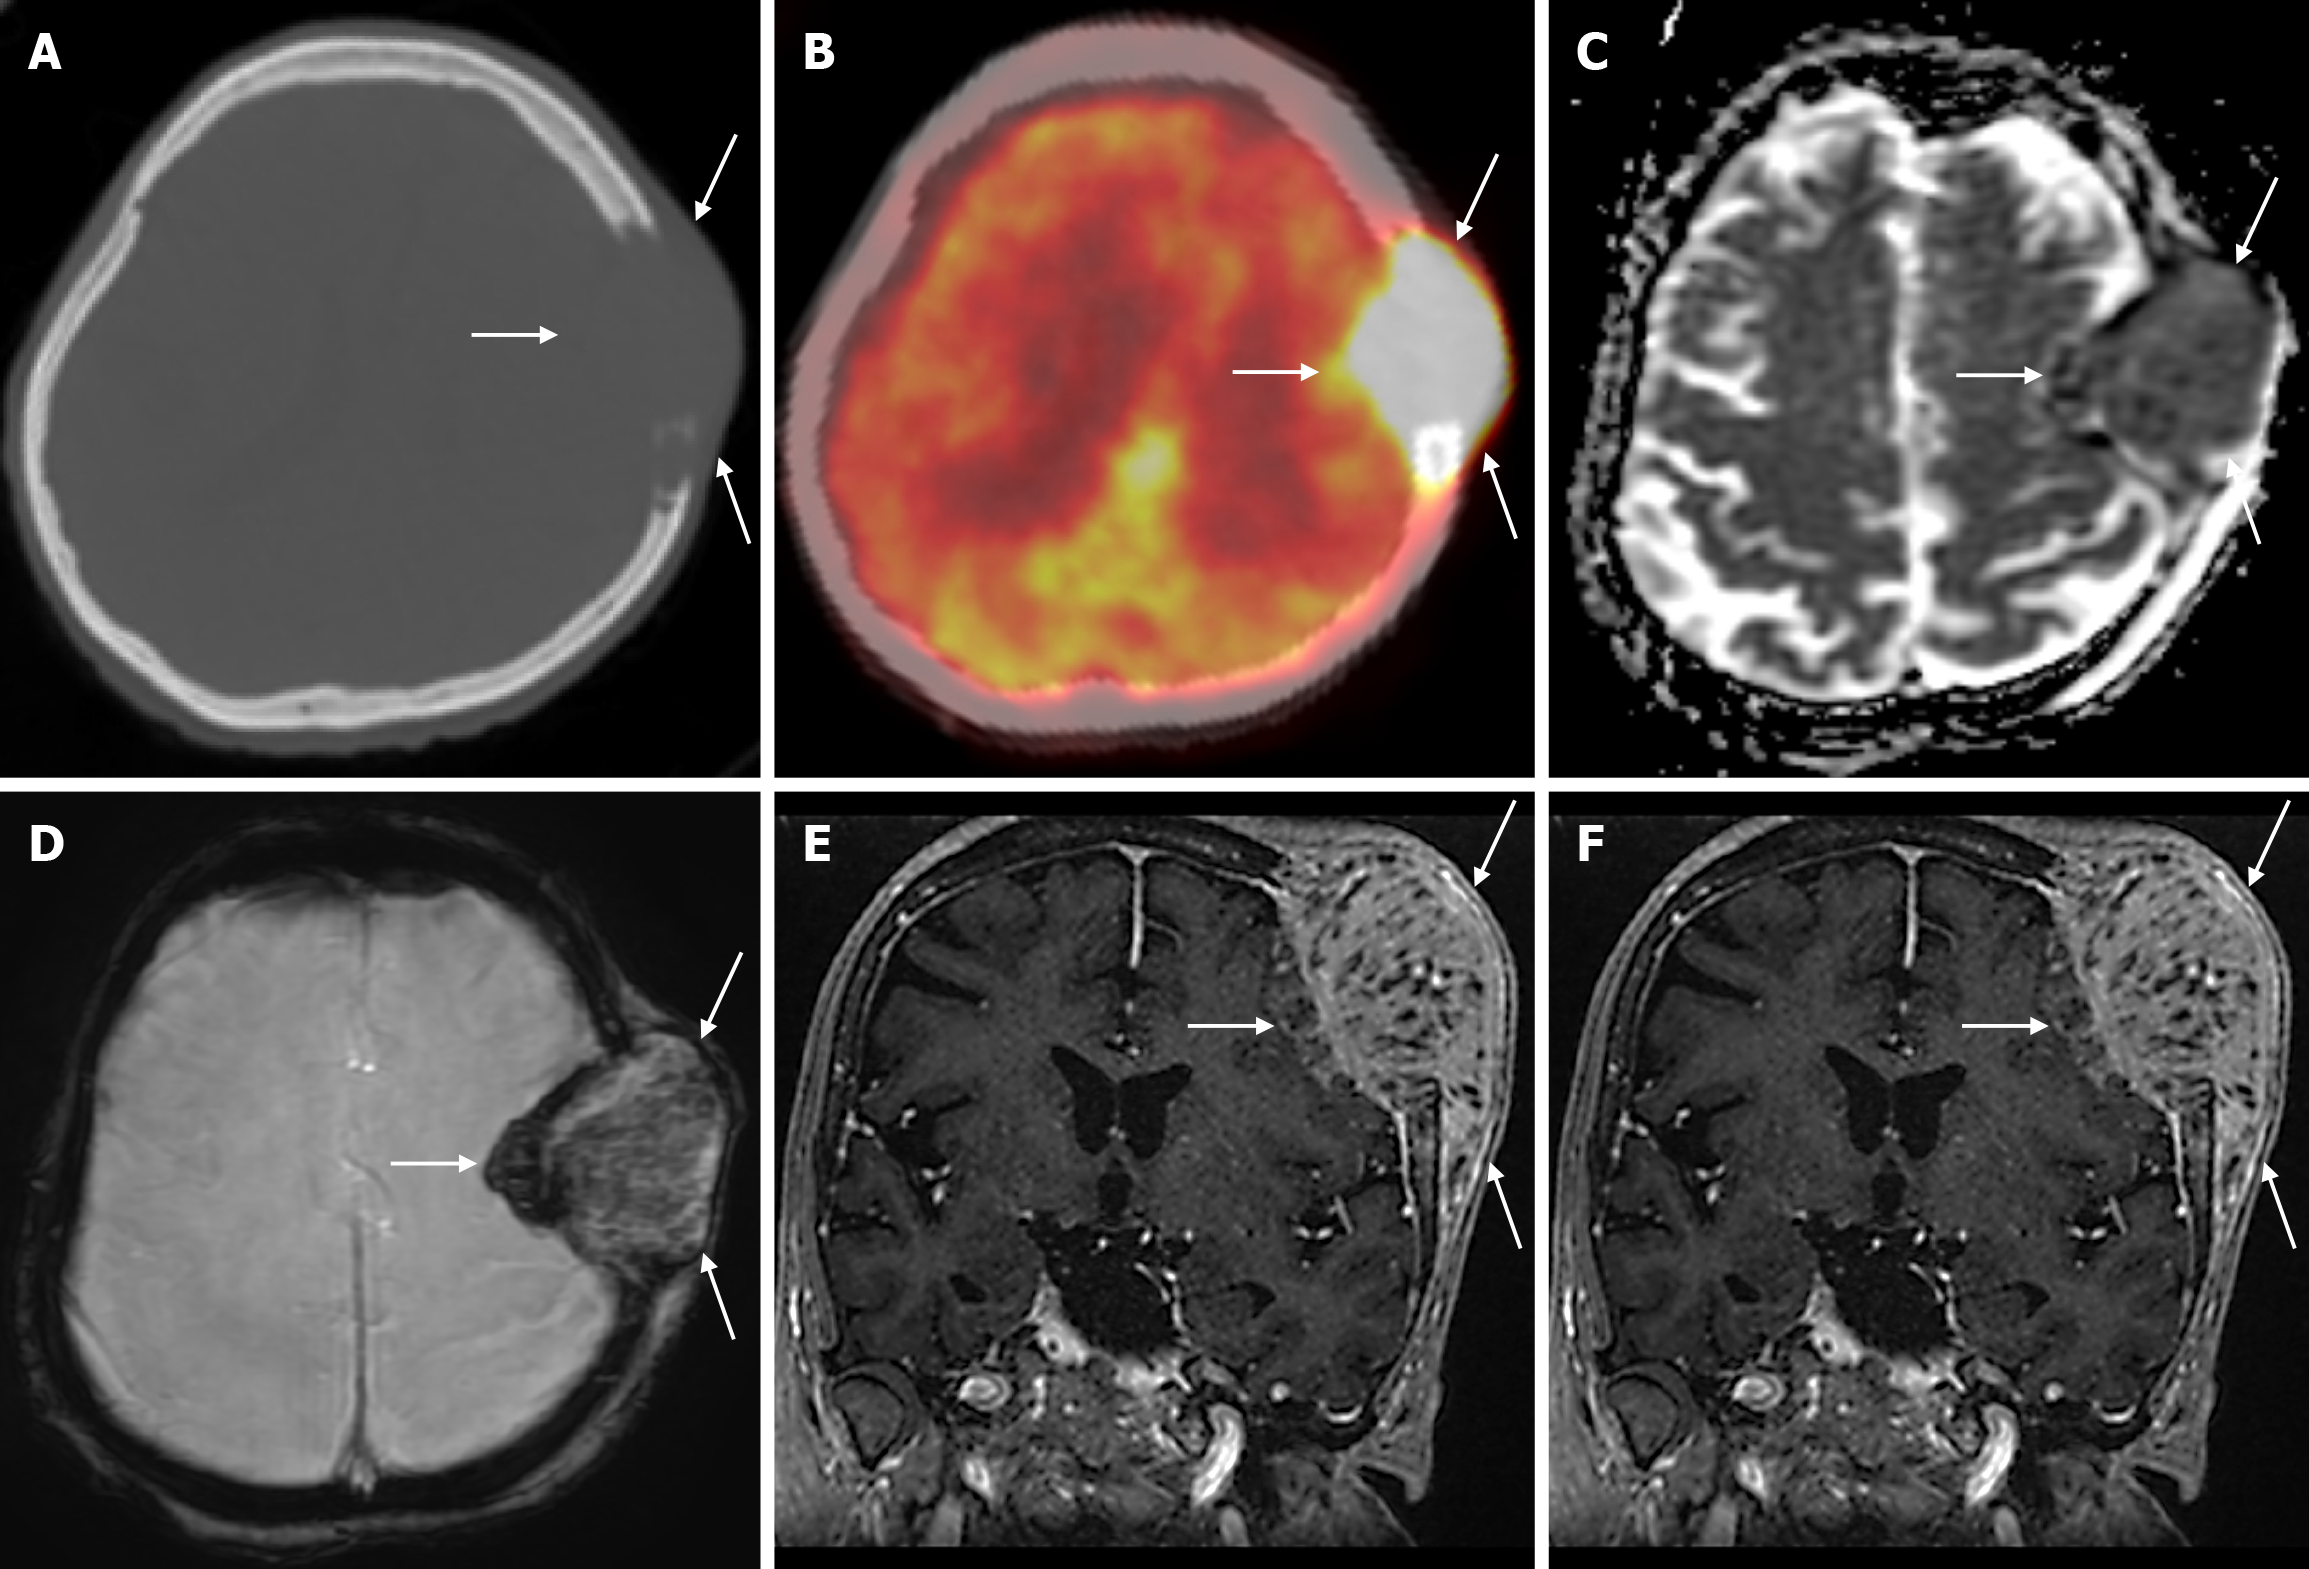

The parietal bone is most commonly involved in the calvarium, followed by the frontal bone. Clinical diagnosis is usually made after palpation of the calvarial mass, and sometimes there may be pain or headache over the mass. The typical finding of Langerhans cell histiocytosis is a round and punched-out lytic lesion. A double-contoured appearance due to irregular destruction of the two tables on plain radiography is highly suggestive of Langerhans cell histiocytosis. On CT, sharply demarcated punched-out lytic lesions involving all three layers of the calvarium are seen in the intradiploic space, with no sclerotic margins or periosteal reaction. The lesion may also appear as beveled edges on CT due to asymmetric involvement of the inner and outer tables. As the lesion regresses, inflammatory cell infiltrates replace the normal bone, and a sclerotic rim can be seen. Granulomas appear slightly dense compared to the grey matter on CT. Residual bone density (button sequestrum) may be seen in the center of the lytic lesion. Lytic lesions may coalesce and a geographic pattern may be seen. MRI is a highly sensitive modality for detecting bone marrow involvement and soft tissue components that may show subgaleal or epidural extension. On MRI, they are hypointense compared to grey matter on T1-weighted images, heterogeneous, hyperintense on T2-weighted images, and show significant contrast enhancement. Dural and galleal reactive contrast enhancement is often seen. Langerhans cell histiocytosis has low apparent diffusion coefficient (ADC) values due to its high cellularity. Healing of lesions, whether spontaneous or with treatment, is associated with centripetal bone formation leading to the progressive disappearance of lesions[7,49-51]. Furthermore, although bone lesions of Langerhans cell histiocytosis usually have typical radiographic features, 18F-FDG PET-CT shows clinically and radiographically more indolent bone lesions[52].